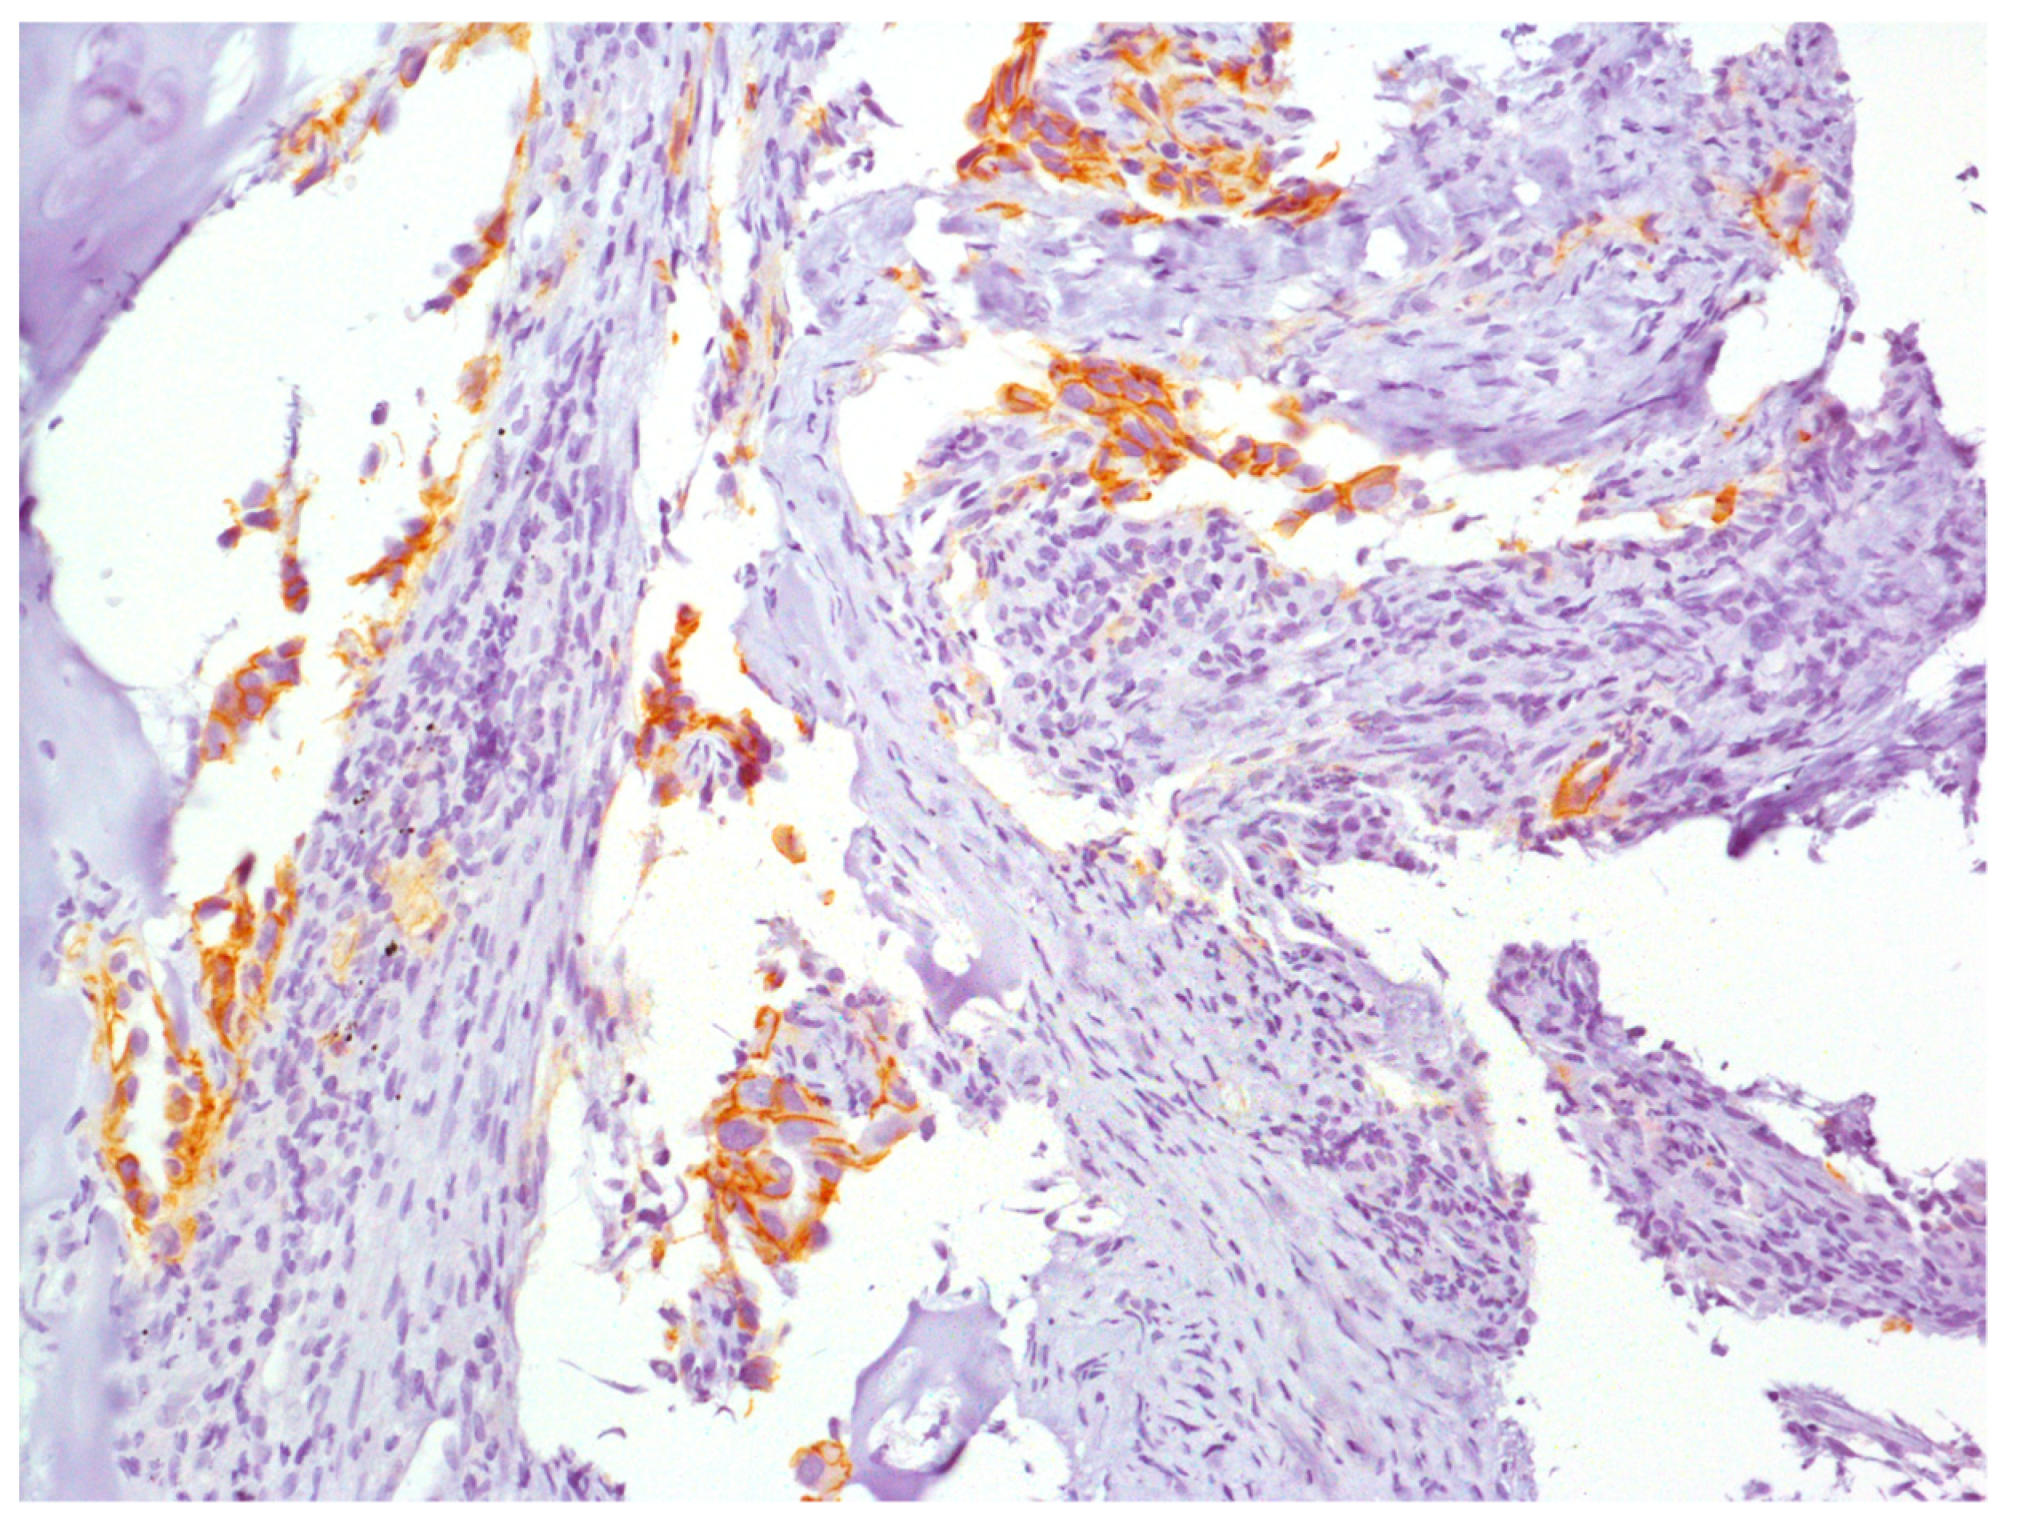

2. Case Report

3. Genetic Analyses

4. Results